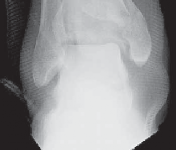

The diagnosis of tibial plafond fracture is initially evaluated with three radiographic views of the ankle (anteroposterior [AP], mortise, and lateral; FIG 4A,B).

These views should be repeated after all “reductions,” including application of temporizing external fixation.

CT scans have been clearly shown to improve a surgeon’s understanding of the injury ( FIG 4C) and are critical to preoperative planning for complex injuries.15

For displaced, comminuted pilon fractures, the best time to obtain a CT scan is after temporizing external fixation is performed ( FIG 4D), when the fracture is brought out to length with traction. This tends to grossly reduce many parts of the fracture, making the pathoanatomy of the injury more understandable (FIG 4E,F).

E F ### FIG 4 • 43-C3 tibial plafond injury. A,B. AP and lateral injury radiographs. C. CT scan. D. “Travelling traction”—early ankle-spanning external fixator. E,F. Radiographs of ankle after closed reduction and application of external fixator. G. Three-dimensional reconstruction of CT angiogram demonstrat- G ing deficient flow through anterior tibial artery.